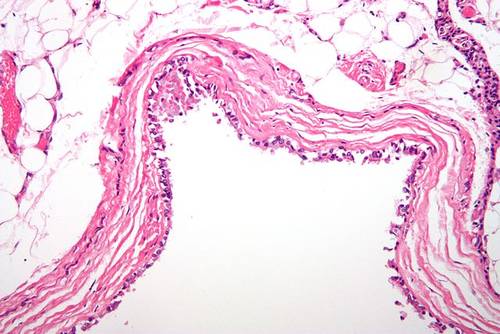

Киста — это патологическое образование в тканях или органах. В зависимости от её формы и расположения имеет различное содержимое. От окружающих структур отделяется капсулой. Иногда стенками кисты является ткань того органа, в котором она находится.

Киста относится к группе доброкачественных образований. Содержимое окружено капсулой. Длительное время никак себя не проявляет. Клиническая симптоматика возникает при значительных размерах образования и если киста является причиной нарушения работы органа.

Доброкачественные опухоли нужно дифференцировать с кистой, поскольку клиника и строение подобны. Если это опухоль, в образце ткани будут выявлены атипичные клетки. При кистозном образовании таких клеток нет, содержимое отвечает локализации.

Единственное, что поможет с точностью ответить, киста это или опухоль, — биопсия ткани и гистологическое исследование.